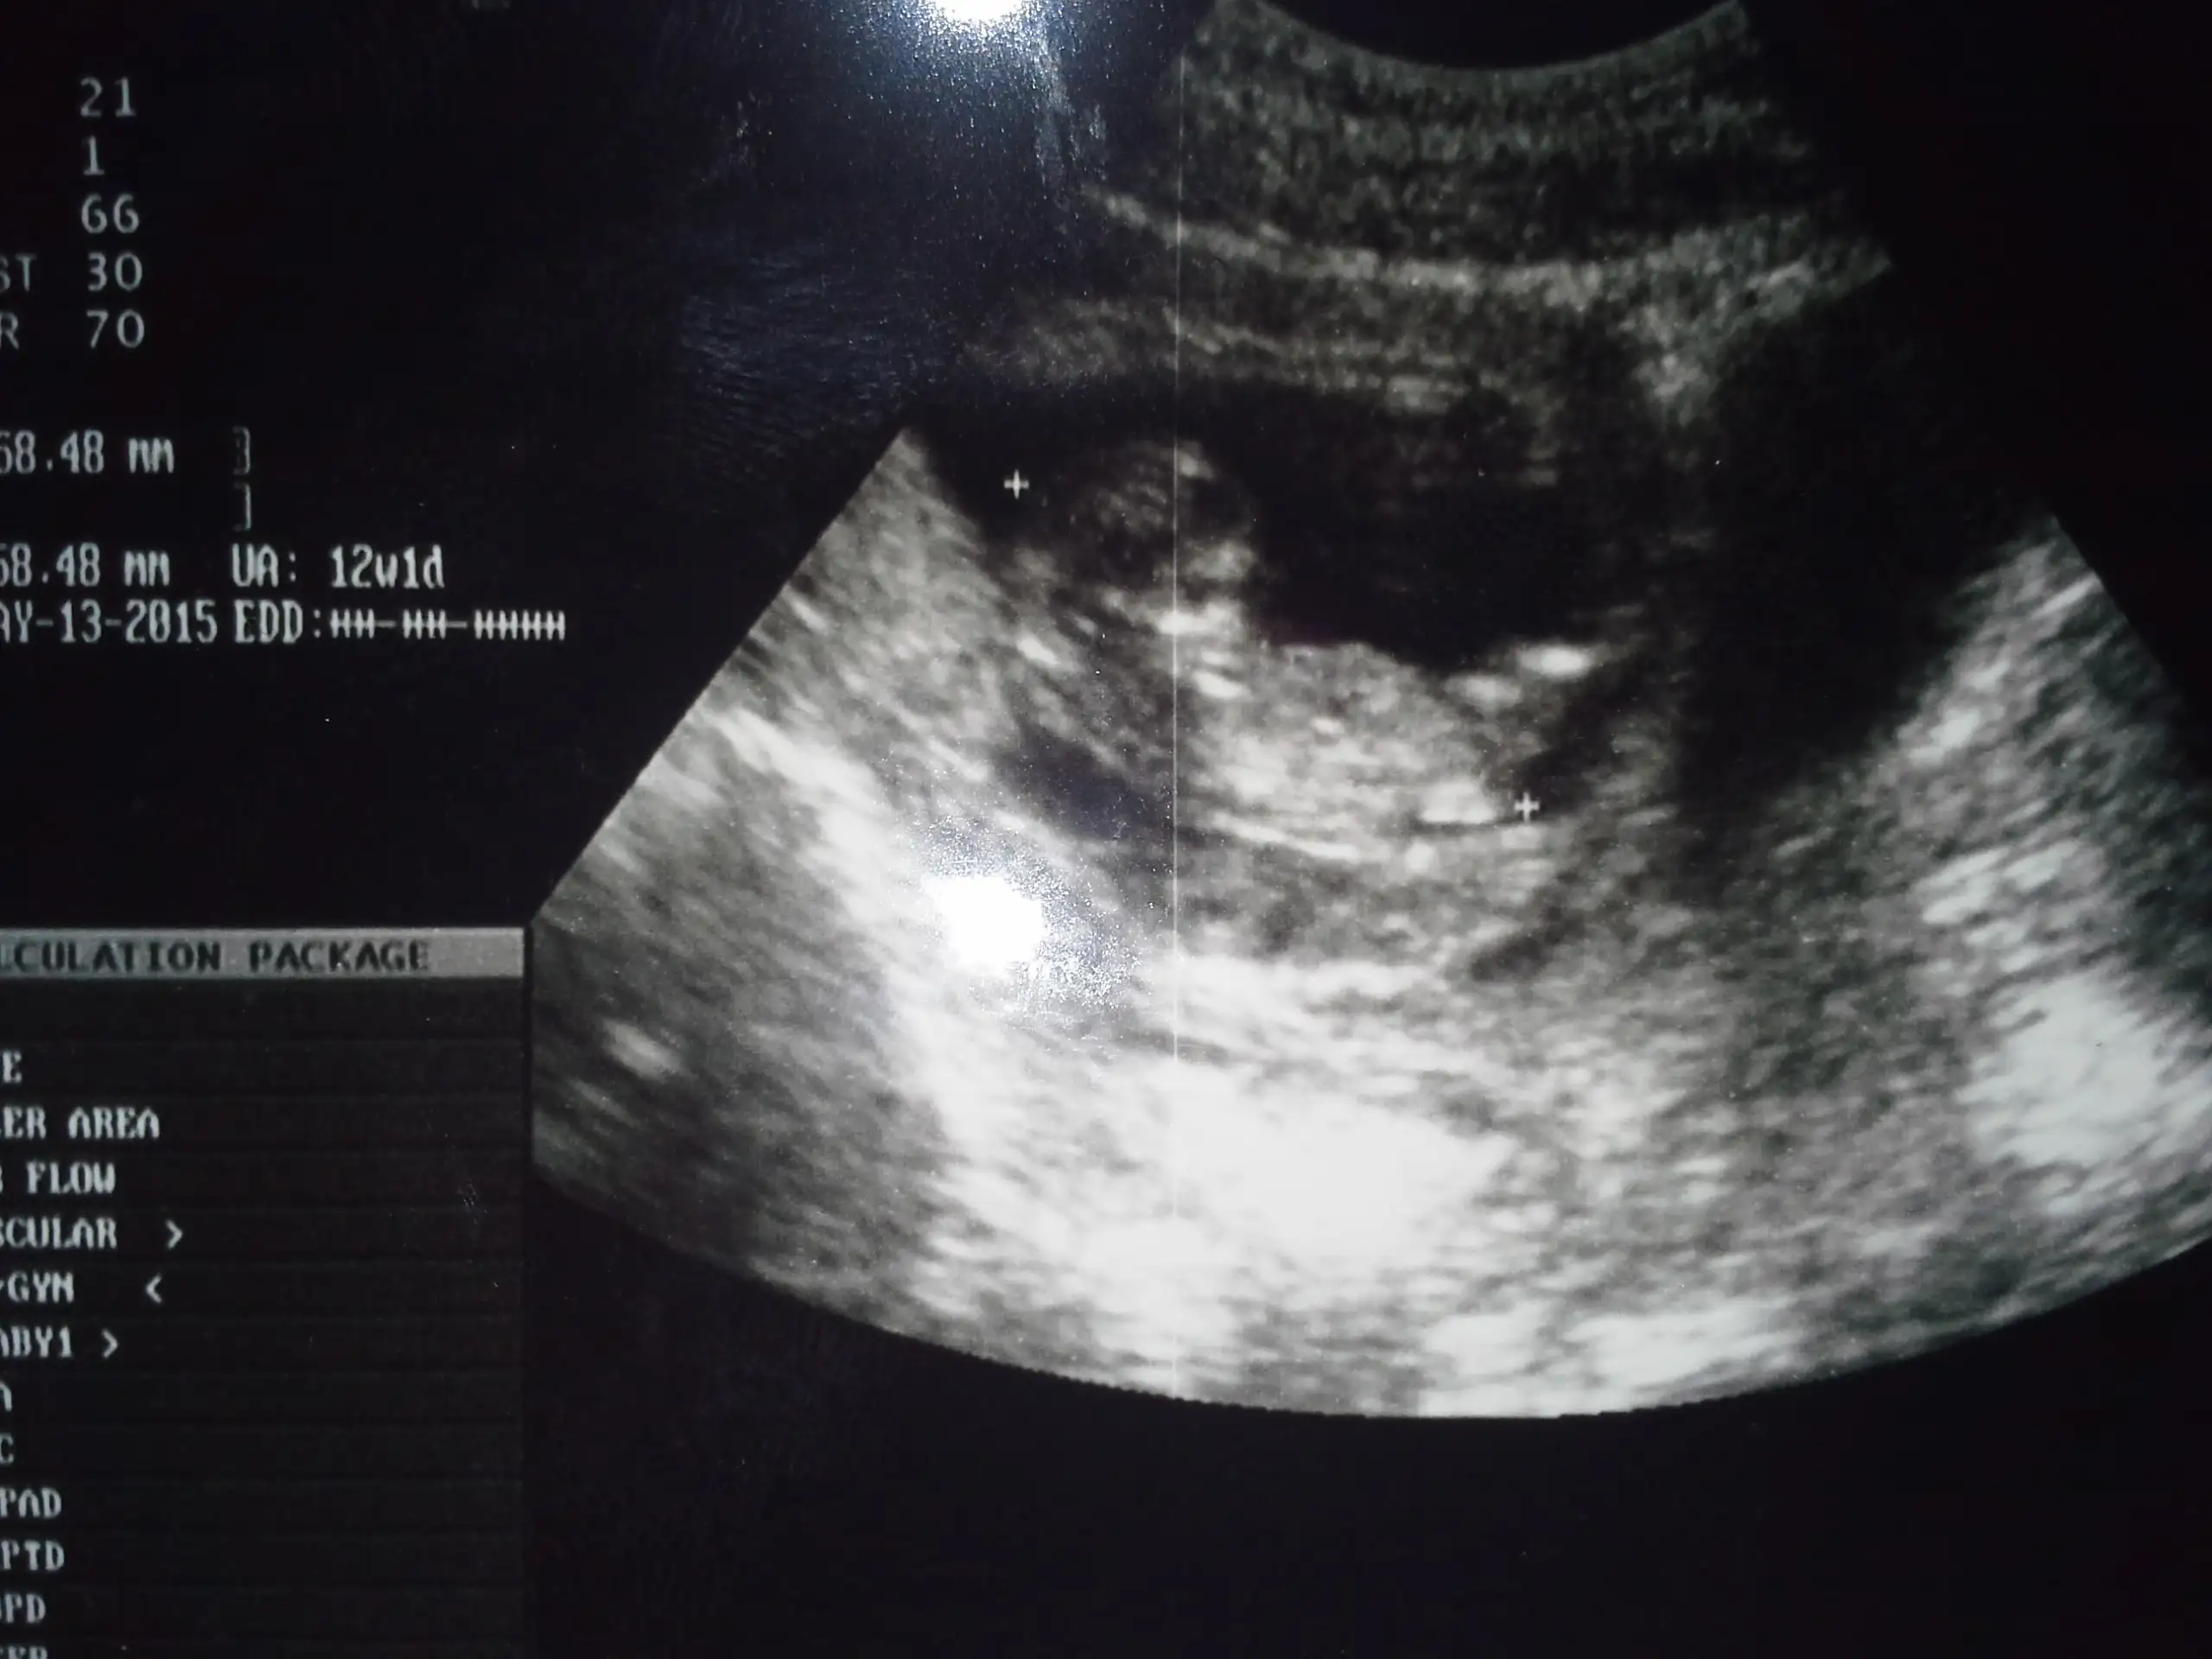

Eklentiler

• 20141030_190325.webp

20141030_190325.webp

105,7 KB · Görüntüleme: 145

• 20141030_185631.webp

20141030_185631.webp

99,3 KB · Görüntüleme: 126

canim kanama alani ne kadarmis?.. Ne dedi doktor.. Bende de vardi 2.5 cm.. Seninki daha kucuk gozuktu bana..

boyutunu söylemedi canım,çok dedi sadece.Bu ultrasom resminde kesenin yanındaki dimi,kesenin yarısı kadar galiba,resimden anlayamadım

,orda ekrandada görüntü çok gidip geliyordu